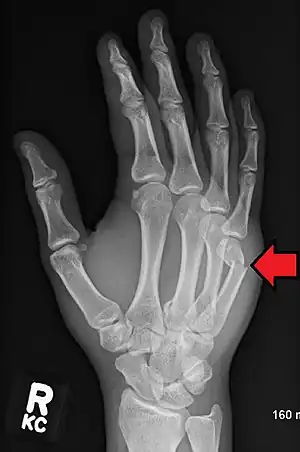

Diagnosis by a doctor’s examination is the most common, often confirmed by x-rays. X-ray is used to display the fracture and the angulations of the fracture. A CT scan may be done in very rare cases to provide a more detailed picture.[8]

Boxer fracture -

Boxer fracture of the 4th and 5th knuckles